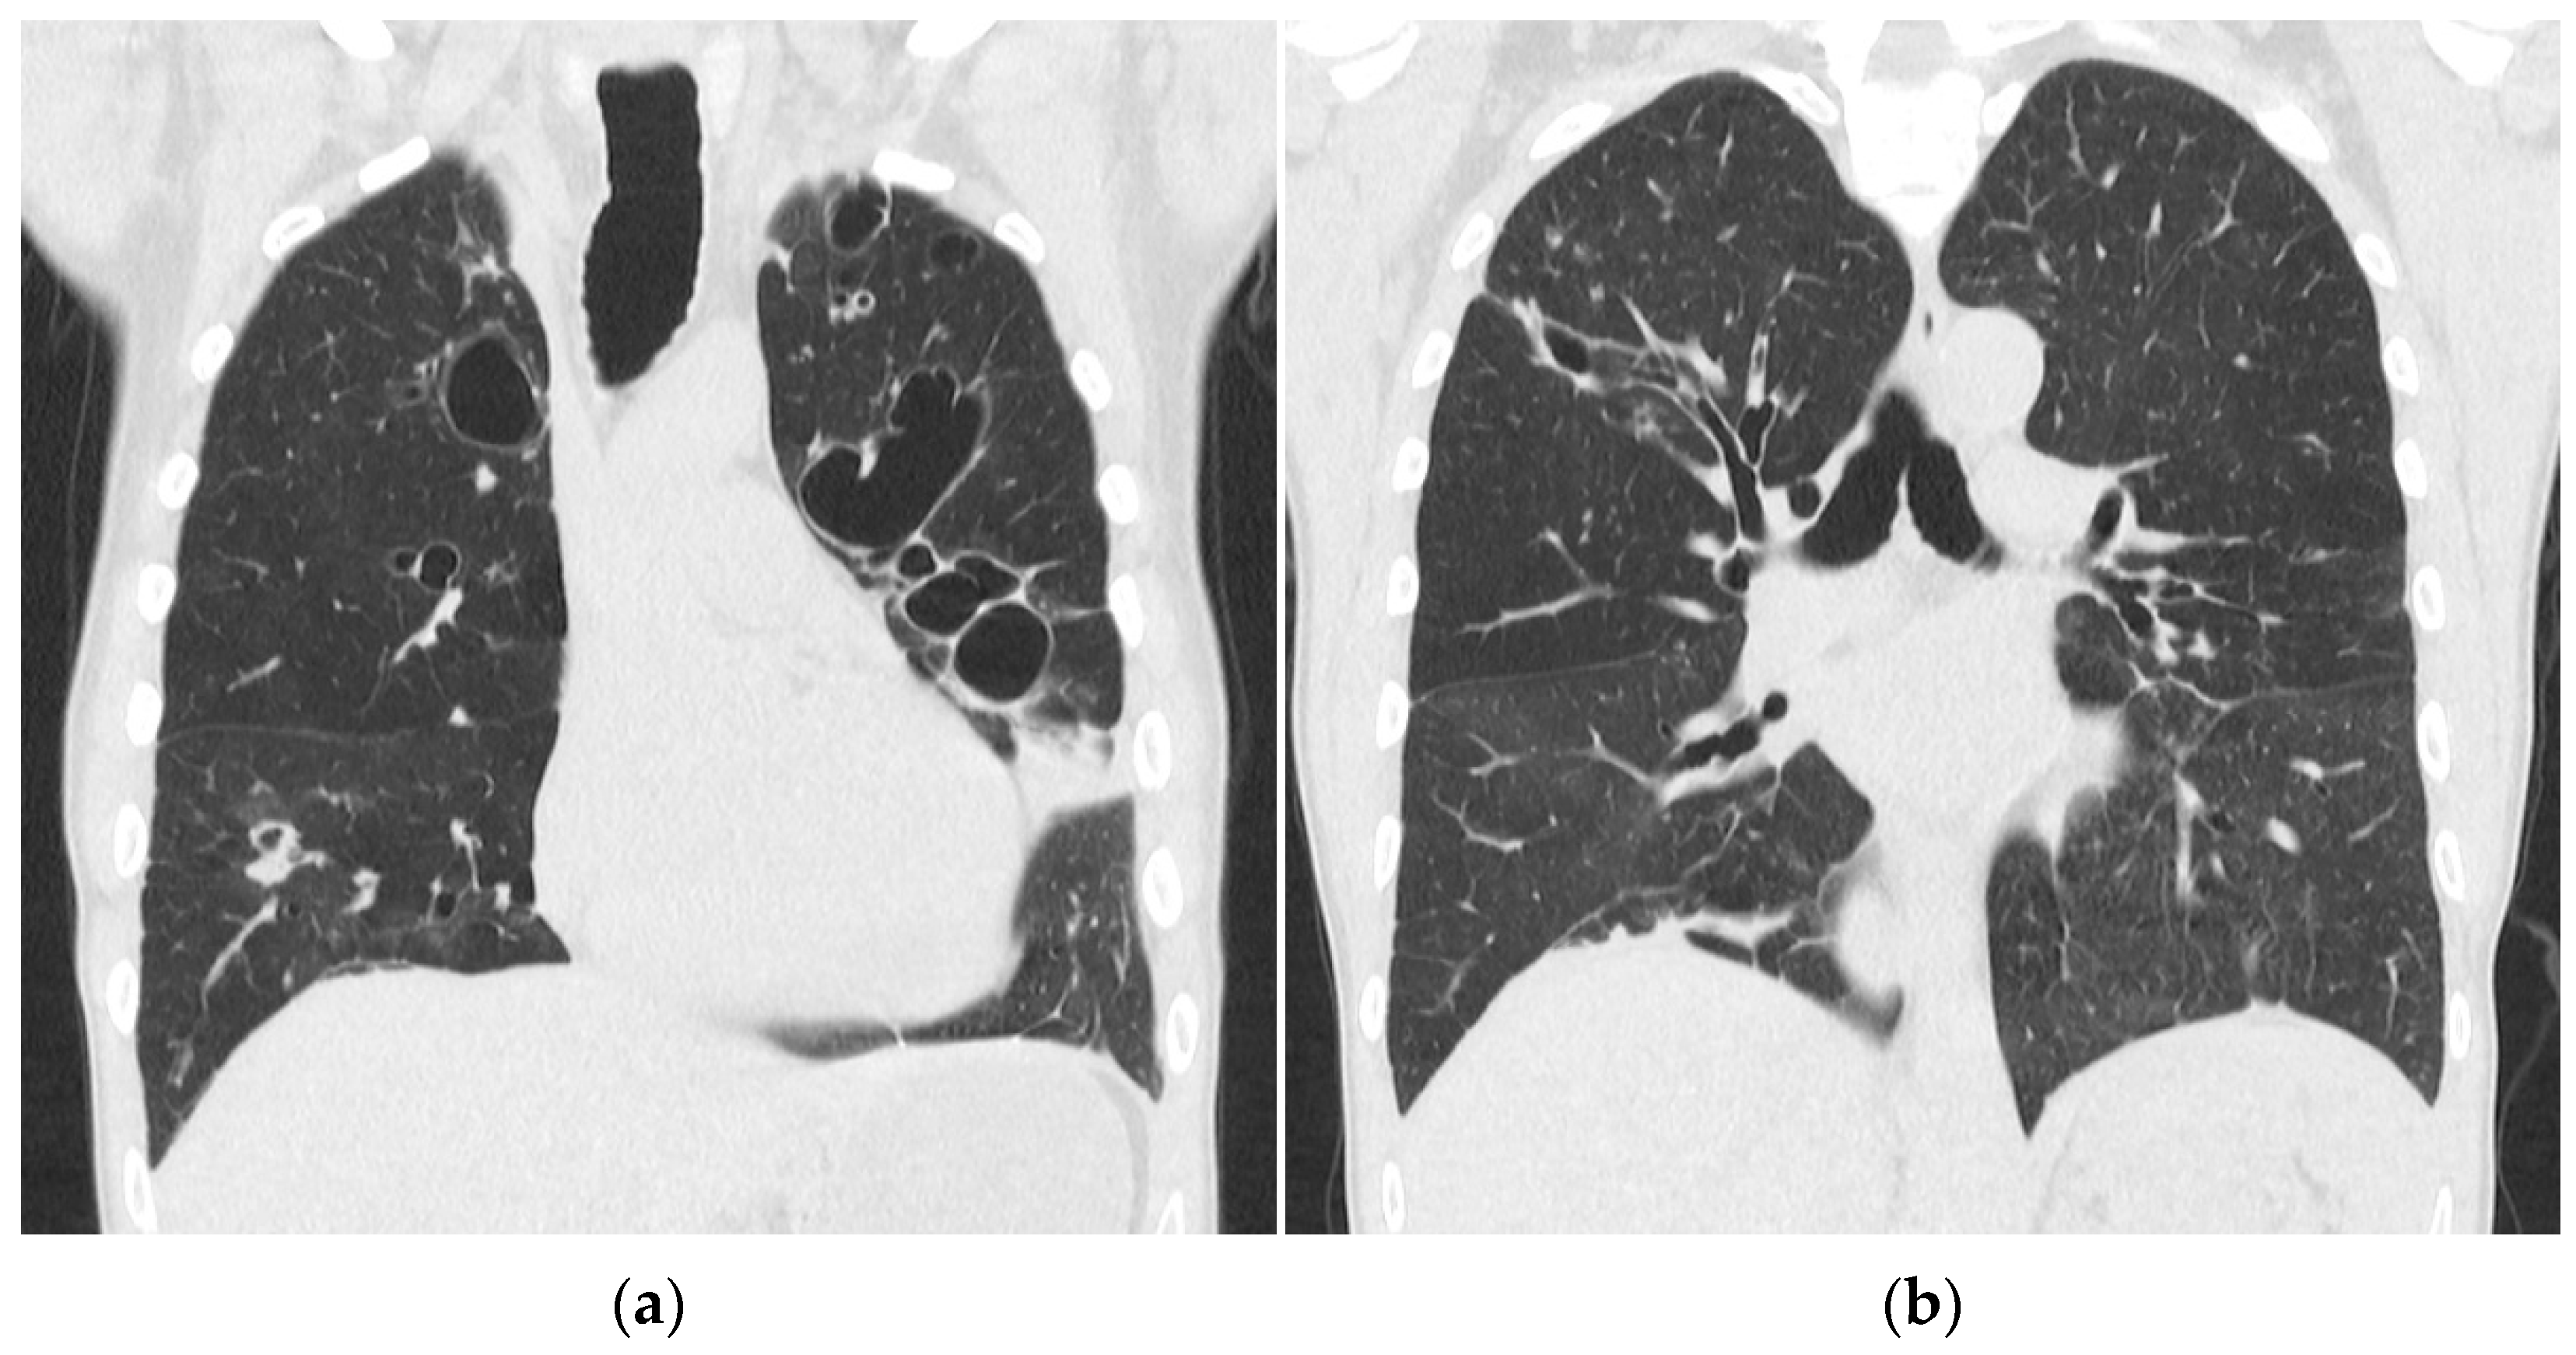

Transthoracic echocardiography showed a left ventricular ejection fraction of 40%. No other abnormalities and no signs of endocarditis were found. A CT scan of the cerebrum, neck, chest, abdomen, and pelvis showed massive bilateral lung infiltrates, atelectasis, and ARDS changes with small amounts of pleural fluids and ascites. No abscesses or infectious foci outside the lungs were found. Figure 2 shows a CT scan of the chest 4 days after admission.

Figure 2. CT scan of the chest with coronal reconstruction. Massive bilateral consolidation with air bronchogram and minimal pleural effusion at day 4.